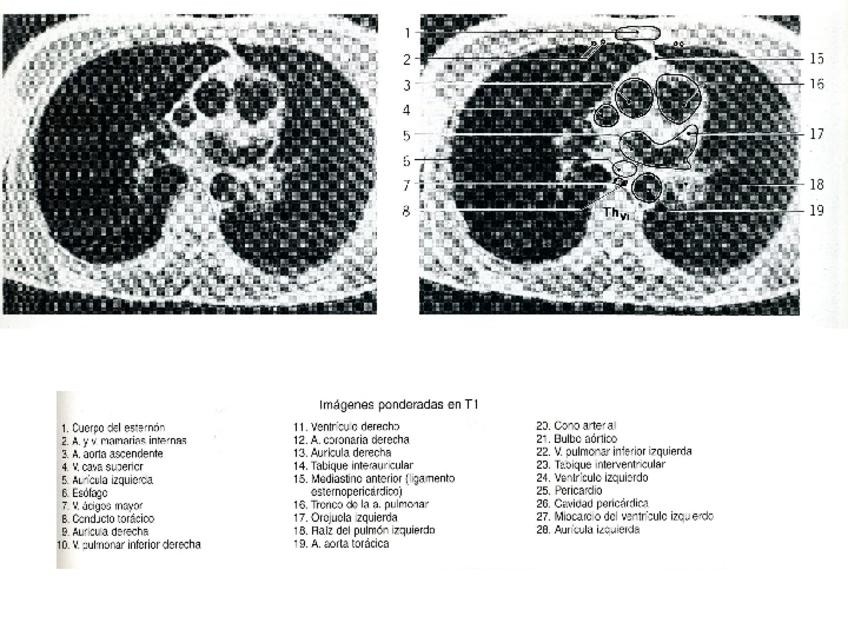

Apuntes - RNMtorax.ppt